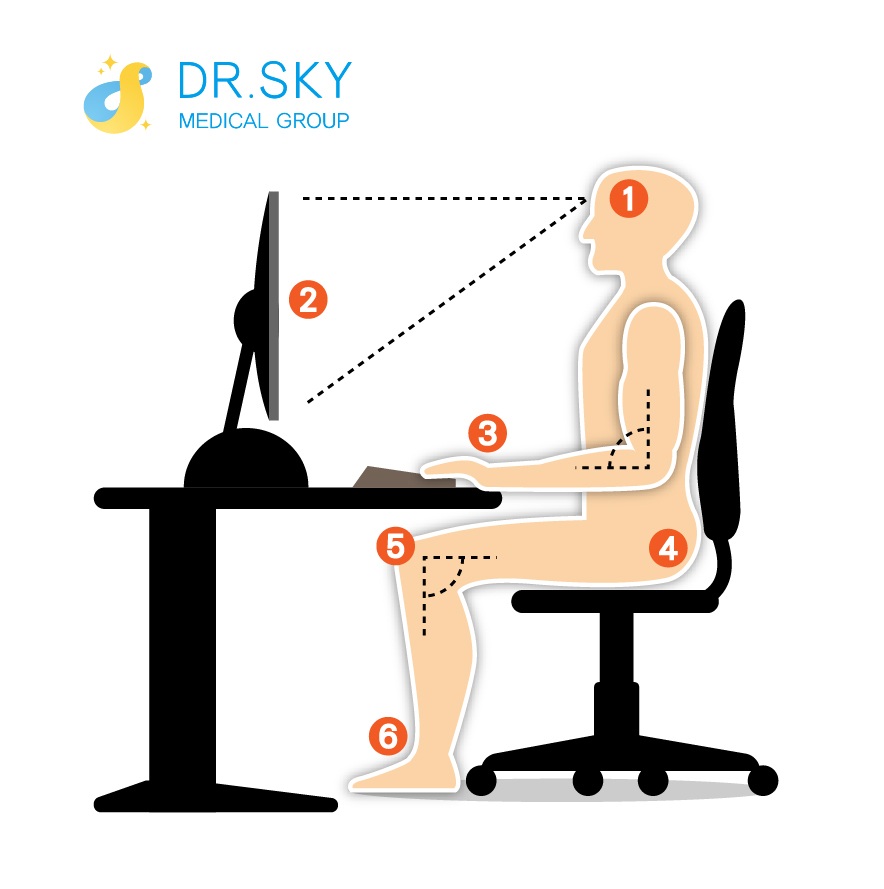

● 姿勢端正

應減少長時間維持固定姿勢(例如:滑手機、低頭看書)的頻率,以避免姿勢不良造成的頸椎急慢性損傷。

2. 電腦螢幕需放置於身體正前方,勿偏歪

3. 手肘彎曲角度約95─110度

4. 椅子盡可能坐深一點

5. 大腿與地面平行,小腿與地面垂直

6. 雙腳踏穩地面,若搆不到地可放小平台墊高